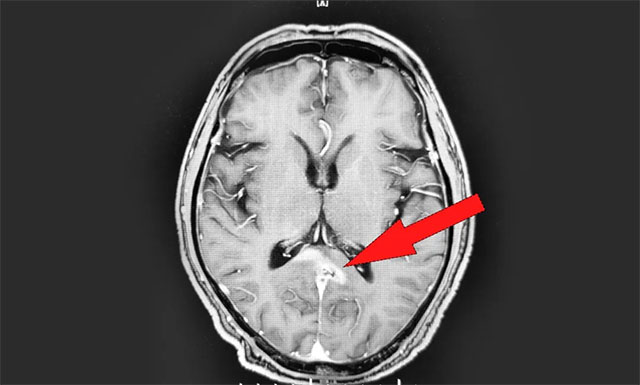

年過六旬的男性患者江某(化名),于2018年進(jìn)行體檢時(shí)被告知脾臟腫大,但由于當(dāng)時(shí)并無不適癥狀,患者沒有太在意。2019年11月中旬,患者突感身體不適,頭暈胸悶惡心,就診于當(dāng)?shù)蒯t(yī)院。行頭顱增強(qiáng)核磁檢查后,診斷其為胼胝體壓部及右側(cè)丘腦淋巴瘤,當(dāng)時(shí)暫未發(fā)現(xiàn)轉(zhuǎn)移跡象。

▲ 放療前 MRI 影像

因病灶位置較深,手術(shù)難度大、風(fēng)險(xiǎn)高;颊吆图覍僭诹私馍虾K{(lán)十字腦科醫(yī)院引進(jìn)了先進(jìn)的瑞典醫(yī)科達(dá) Synergy 數(shù)字化直線加速器,并擁有經(jīng)驗(yàn)豐富的放療專家團(tuán)隊(duì)后,便慕名來醫(yī)院尋求放射治療。